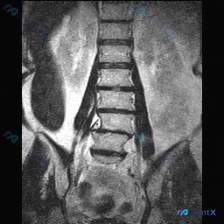

网上看到一份标注为「脊柱侧凸」的腰椎MRI T1冠状位资料,整理了影像分析的核心信息,想和大家讨论一下。

目前的影像表现:

- 腰椎各椎体(L1-L5)轮廓基本完整,无明显楔形变、压缩或骨质破坏

- 冠状位力线尚可,未见明显的侧弯畸形,椎间隙高度基本维持

- 双侧腰大肌对称,肌纤维信号未见明显异常,无明确巨大占位

- 椎体骨髓信号基本均匀,未见典型局灶性低信号或「蜂窝状」高信号

但问题在于:这份资料被标注了「Scoliosis(脊柱侧凸)」,和影像报告的客观描述存在矛盾。